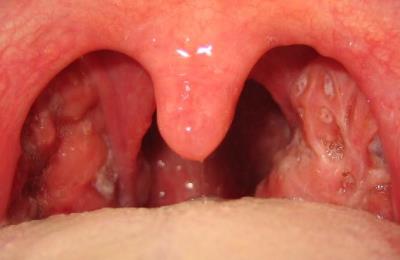

Проявления хронического тонзиллита:

- покраснение краев небных дужек;

- разрыхление и уплотнение миндалины;

- наличие гнойных пробок;